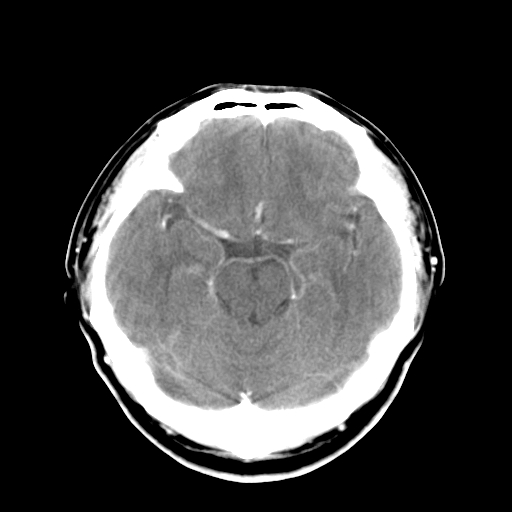

标题: CT16447B:(续)增强扫描图像。

患者今日做ct增强检查,现补传增强扫描图像。

松果体钙癍增大,无其他改变,定不了性

一般认为大于1cm为异常。